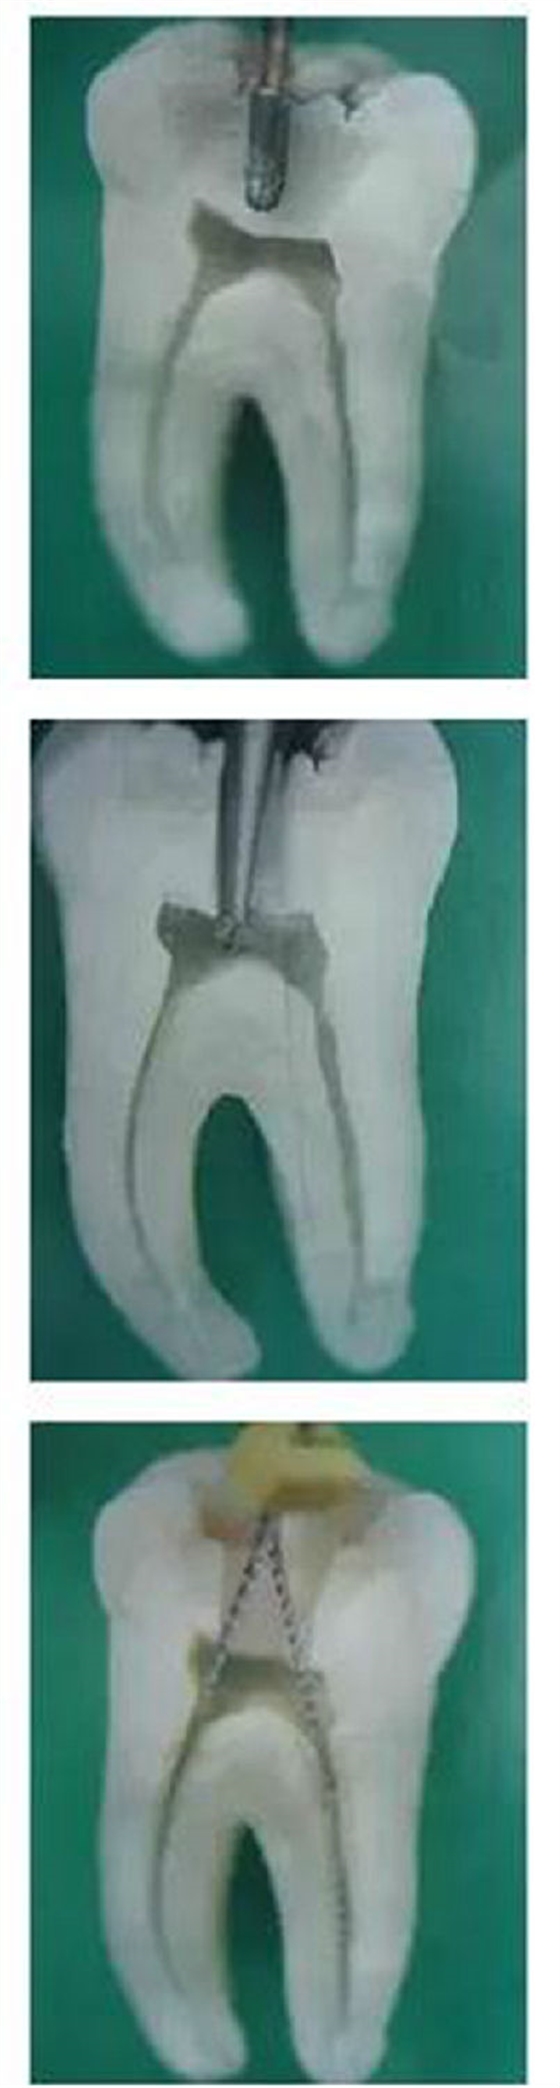

圖1,裂鉆鉆到近髓 2,球鉆穿髓 3,小號(hào)銼探查根管口

圖4,球鉆揭髓頂 5,修整洞型 6,完成開髓

再次分享根管治療的點(diǎn)滴見解!再次分享根管治療的點(diǎn)滴見解!再次分享根管治療的點(diǎn)滴見解!

1,彎曲根管冠部處理之前;2,用GG鉆或SX銼進(jìn)行預(yù)備;3,處理后形成的直線通道

我的病例1_____冠部處理成直線通道后的充填效果